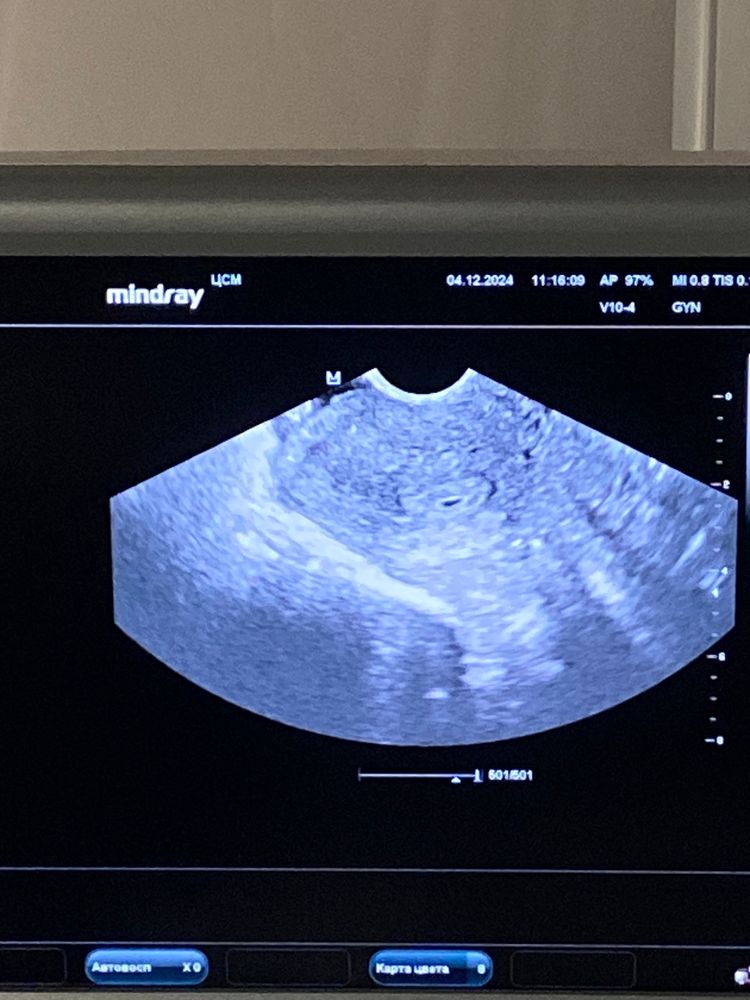

ТонусЗдравствуйте, сегодня была была на первом узи. 4 день задержки, овуляция была 14.11. Пя в матке, но гинеколог сказала что есть тонус. На узи сама вижу, пя мне кажется деформировано .. гинеколог на этот счет ничего не сказала, выписала утрожестан 300, до этого вставляла 200 и сказала могу симптоматически пить ношпу/вставлять папаверин. Кто чем снимал тонус ? Боюсь зб, так как первая беременность ей и закончилась тоже был тонус…

фото узи прикрепила